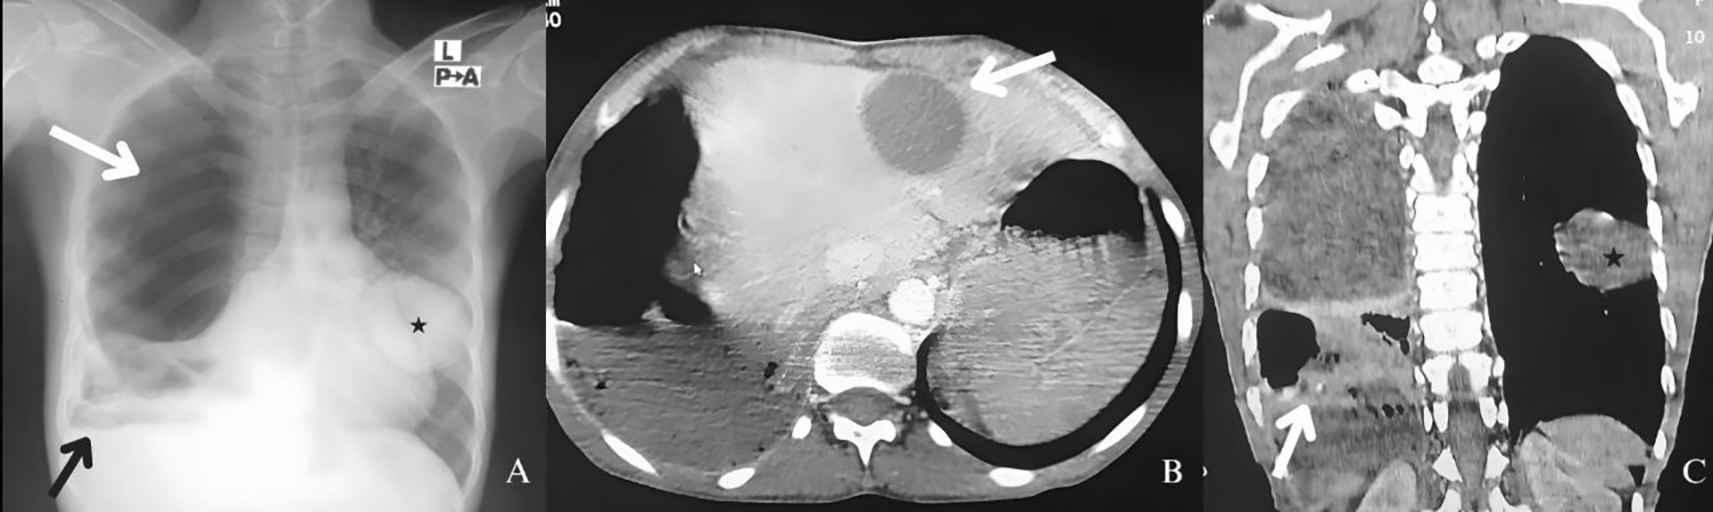

Due to the conflict in Khartoum, a 45-year-old woman was compelled to relocate to Sinnar, Sudan, an area known for its abundance of domestic animals such as sheep, dogs, and goats. After two months of residence, she began experiencing symptoms of shortness of breath, chronic cough, and weight loss. The patient presented with fever and was found to have an erythrocyte sedimentation rate of 130 mm per hour, a C-reactive protein level of 88 mg per liter, and a white blood cell count of 33750 per cubic millimeter with 88% neutrophils (Table 1). A lung abscess was detected on her chest X-ray, leading to empyema, pneumothorax, and pleural effusion in the right lung (Figure 1A). Additionally, an unidentified round-shaped lesion was observed in the left lung (Figure 1A). Due to the limited resources in the area, including a lack of radiologists, technicians, and reliable power supply, physicians diagnosed the patient clinically with pulmonary tuberculosis and this was further confirmed by sputum analysis yielding acid fast bacilli. The appropriate treatment was initiated, including intravenous antibiotics and chest tube insertion for draining the empyema. She was discharged with anti-tuberculous medication and advised to return for a follow-up in two weeks.

The patient was readmitted due to upper abdominal fullness and a palpable mass in the liver. Abdominopelvic ultrasound indicated the presence of a cystic lesion in the left liver lobe, which was further confirmed by computed tomography showing a solitary thin-walled cystic lesion at segments two and four (Figure 1B). Evaluation of chest Computed tomography (CT) revealed loculated pneumothorax, round lung collapse, and adjacent pleural thickening (Figure 1C). A test using enzyme-linked immunosorbent assay revealed an anti-echinococcus IgG antibody index of 16.8 in the patient’s serum supporting the diagnosis of Echinococcosis, as well as reactivation of pulmonary Tuberculosis. The patient responded well to Albendazole treatment, and her symptoms resolved. Surgical intervention was done, and a follow-up ultrasound sound showed no signs of recurrence. The possibility of pleural decortication was considered to facilitate lung re-expansion.